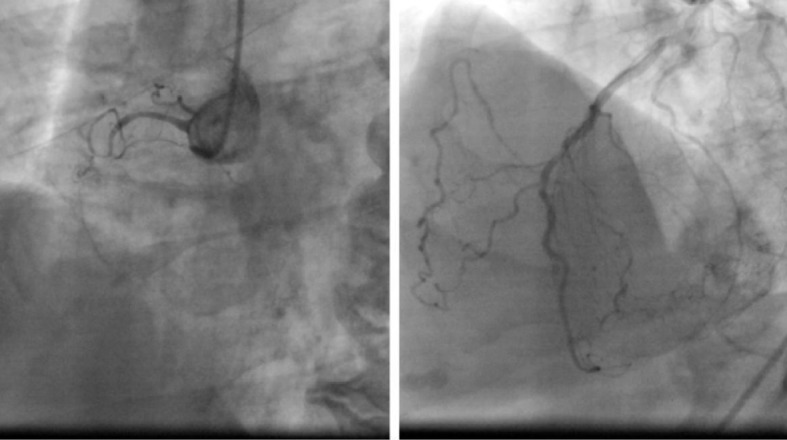

We would like to represent a case of a 68-year-old man who was hypertensive, tobacco chewer presented with chest pain and dyspnea on exertion since 6 months ago with baseline electrocardiogram (ECG) within normal limit (Fig. 1), no significant finding on chest X-ray (Fig. 2); but had positive stress imaging, so we had coronary catheterization of this patient which revealed mid RCA total occlusion and distal RCA filling retrogradely from left coronary artery (Fig. 3).

Figure 3.

Coronary angiography of the same patient showing chronic right coronary artery total occlusion with left coronary shoot revealing retrograde flow to RCA.